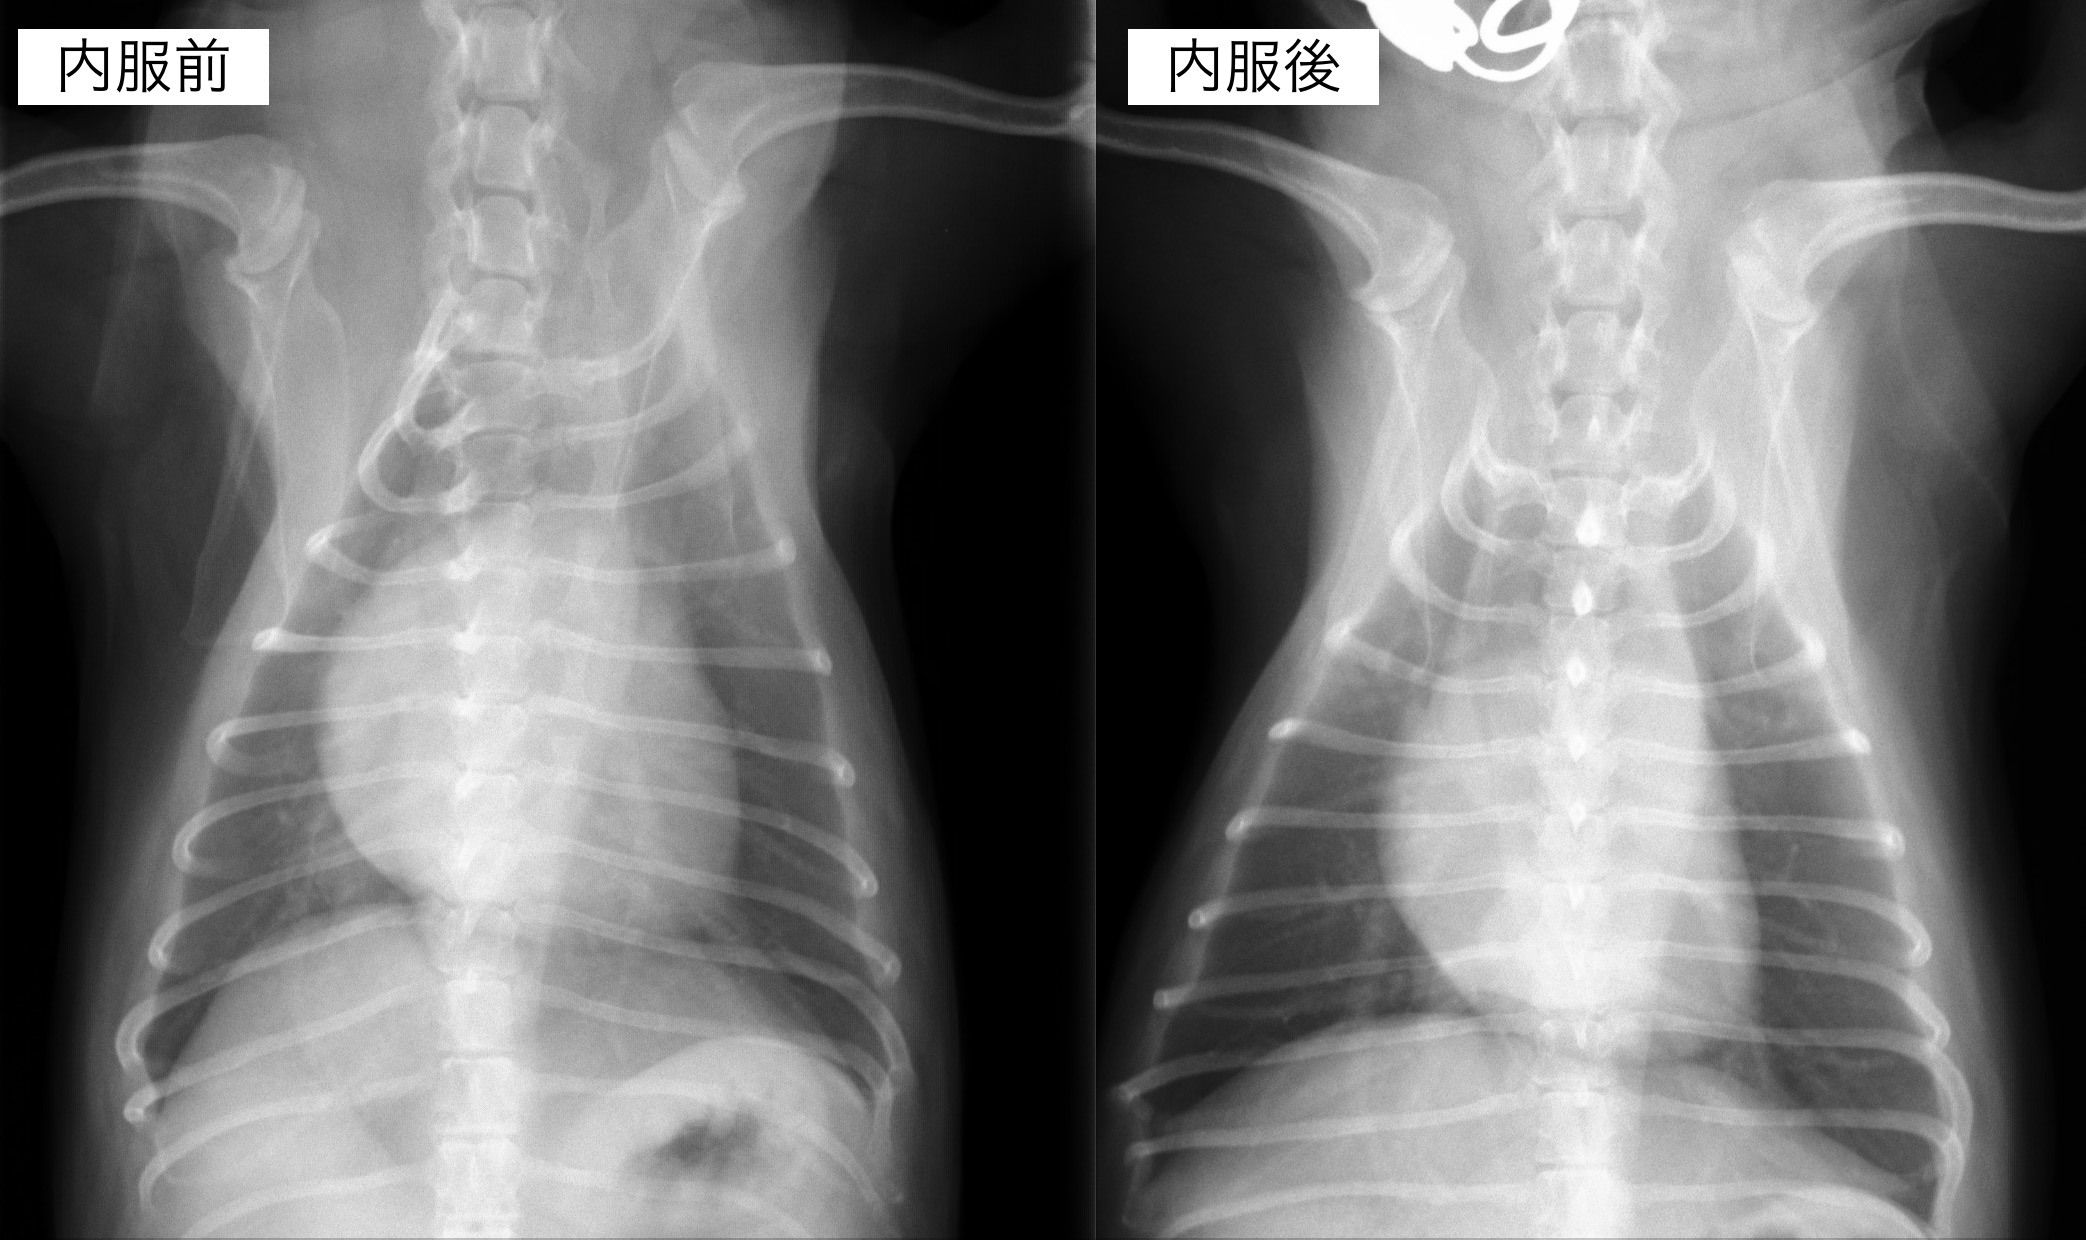

聴診検査にて心雑音が観察され、レントゲンん検査では心臓の明らかな拡大が認められました。

内服開始1ヶ月後のレントゲン検査です。

心臓の拡大はやや改善しており、咳の頻度も減っているとのことでした。